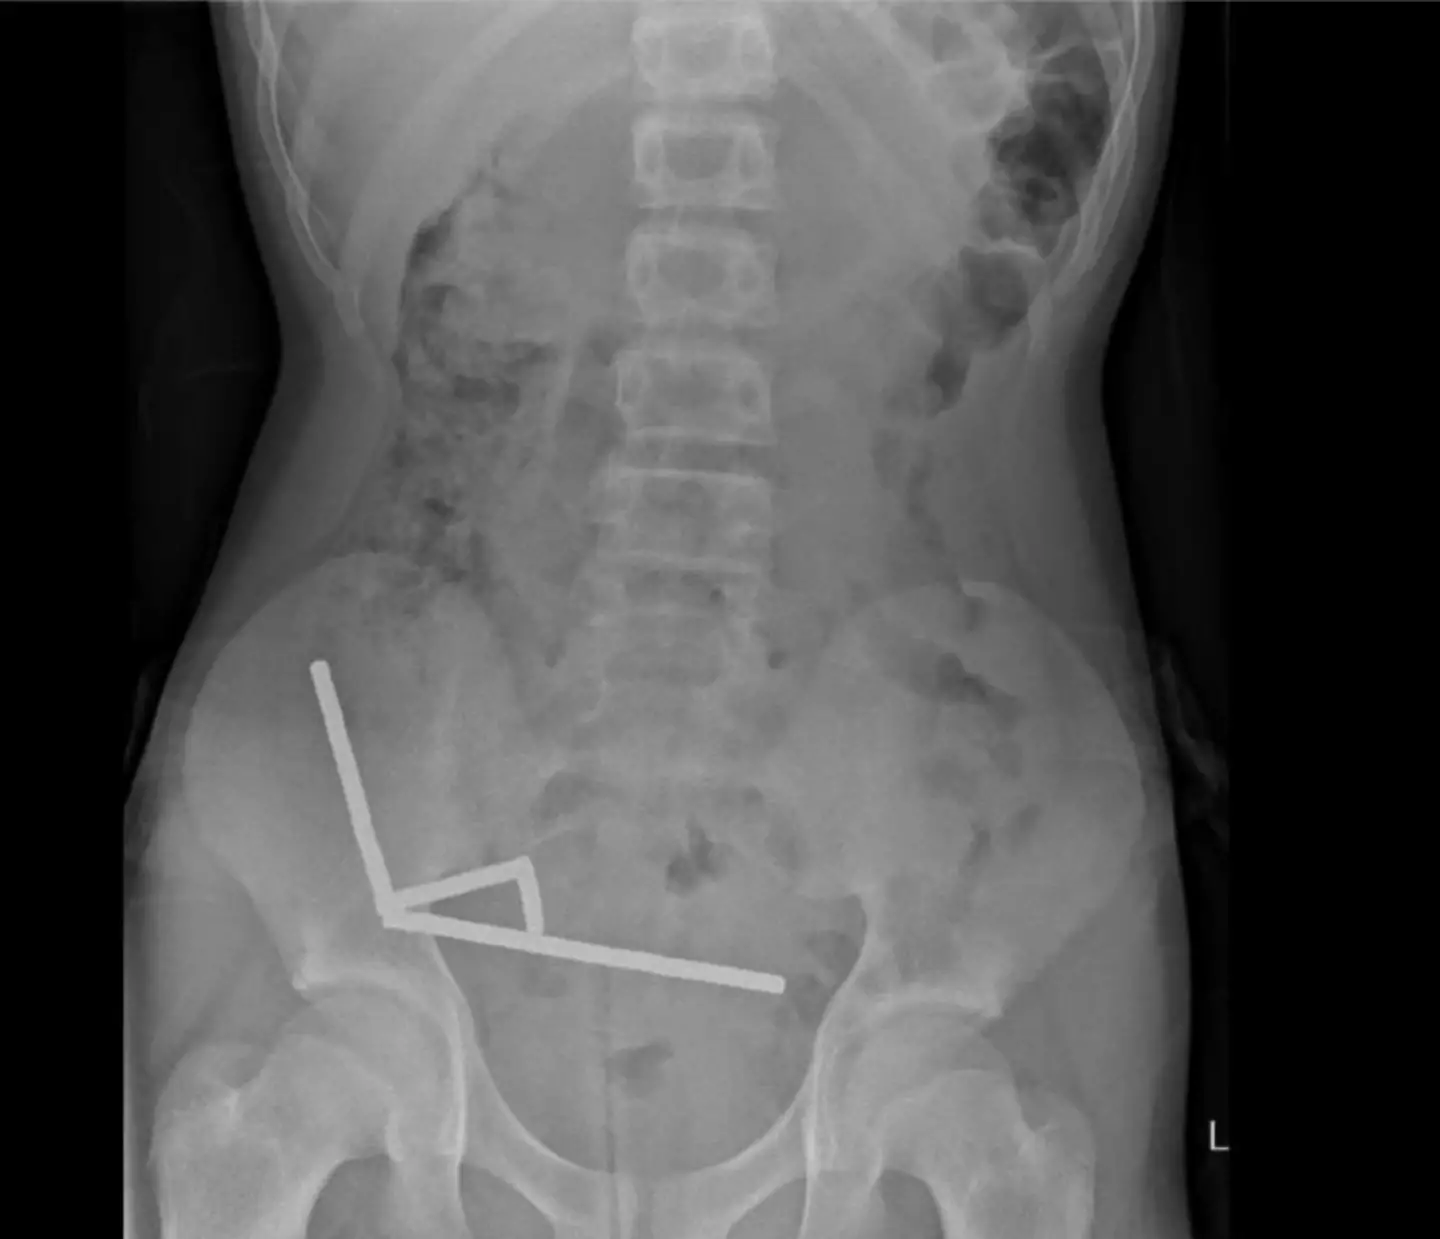

X-rays then revealed that the magnets - which have been banned in New Zealand since 2013 - were connected in 'four linear chains' inside his intestines.

The doctors behind the report, Binura Lekamalage, Lucinda Duncan-Were and Nicola Davis, wrote: "These appeared to be in separate parts of bowel adhered together due to magnetic forces."

"Intraoperative findings were of several chains of magnets at different segments of small bowel and caecum," it continued. "These were adhered at multiple points in the right lower quadrant causing pressure necrosis."